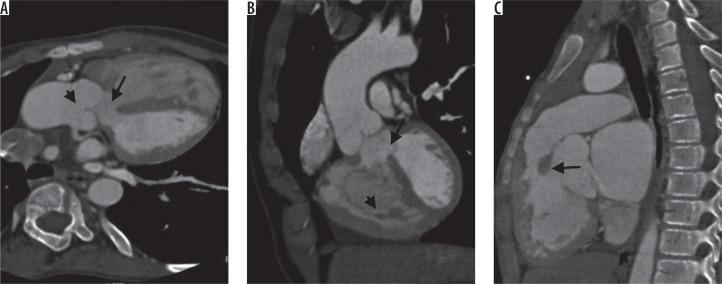

法洛四联症患者右心室流出道梗阻及其他相关心血管异常的多排螺旋计算机断层扫描血管造影评估

Multi-detector computed tomography angiographic evaluation of right ventricular outflow tract obstruction and other associated cardiovascular anomalies in tetralogy of Fallot patients.

To evaluate various types of right ventricular outflow tract obstruction associated with tetralogy of Fallot (TOF) with emphasis on the abnormality of pulmonary arterial system and other associated cardiovascular anomalies using computed tomography (CT) angiography.

利用计算机断层扫描(CT)血管造影术评估与法洛四联症(TOF)相关的各类右心室流出道梗阻,重点关注肺动脉系统异常及其他相关心血管畸形。

漏斗部合并肺动脉瓣狭窄是最常见的狭窄类型(47.28%),其次是单纯漏斗部狭窄(34.23%)。还发现了左右肺动脉的孤立性异常。右侧主动脉弓(23.91%)是最常见的相关异常,其次是双上腔静脉(9.78%)。

TOF与各类右心室流出道梗阻相关,范围从漏斗部狭窄到右或左肺动脉的孤立性狭窄,还与心血管系统的各种其他先天性异常相关。CT血管造影术是一种出色的成像方式,可对与TOF相关的各种异常进行全面分析。